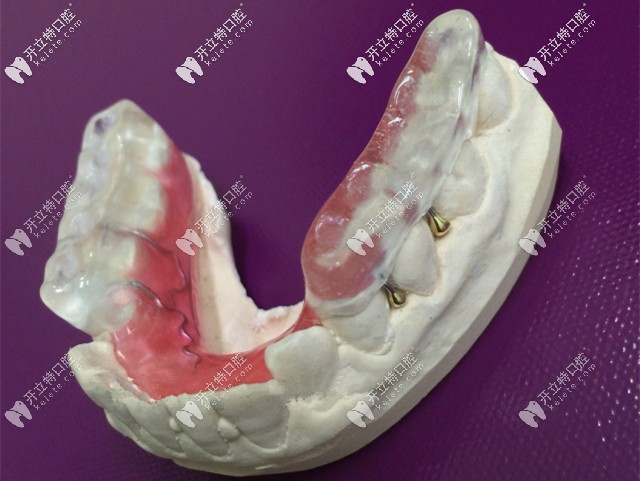

后牙做頜墊打開(kāi)咬合

為顧客做咬合記錄,送到加工廠制作后牙頜墊